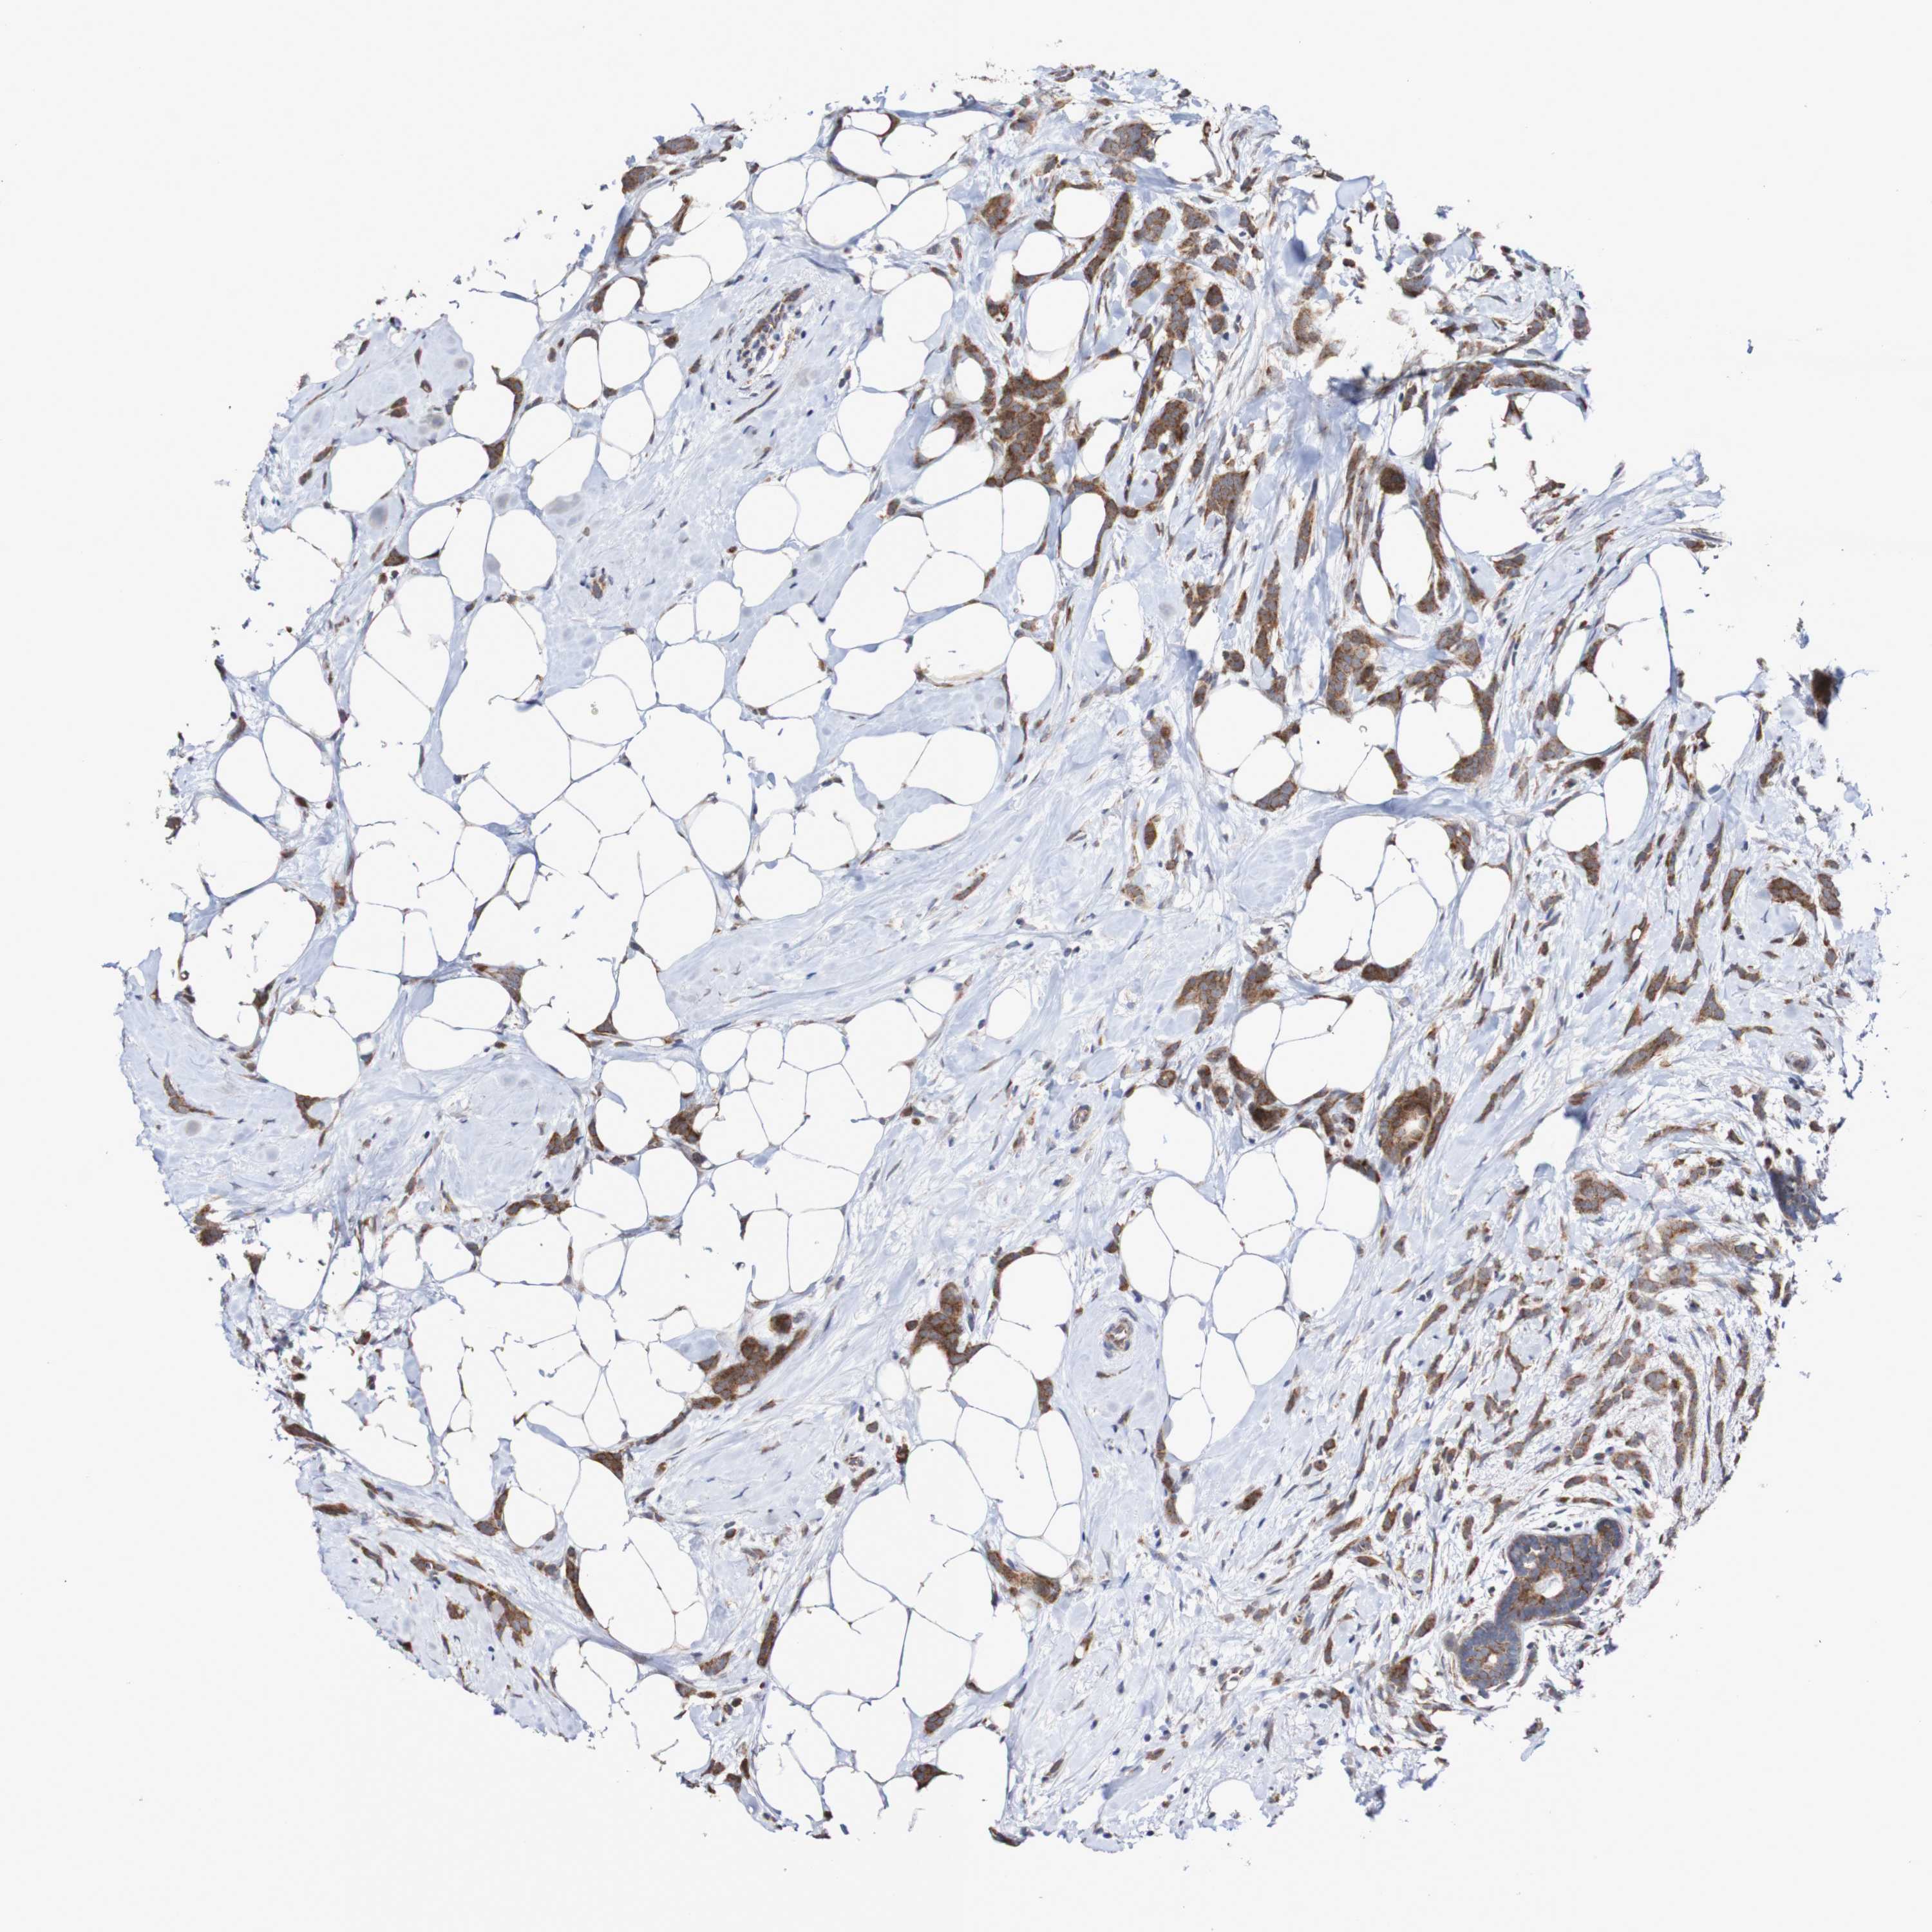

CANCER BREAST CANCER Show tissue menu

BRCA TCGA BRCA VALIDATION PROTEIN EXPRESSION